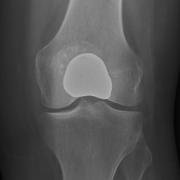

Tibiofemoral UKR.

This has the benefit of relieving pain in an affected area, while allowing the dynamics of the unaffected parts of the knee to remain unaffected.

A unicompartmental knee replacement is a surgical procedure where the surgeon just replaces one part of an arthritic joint.